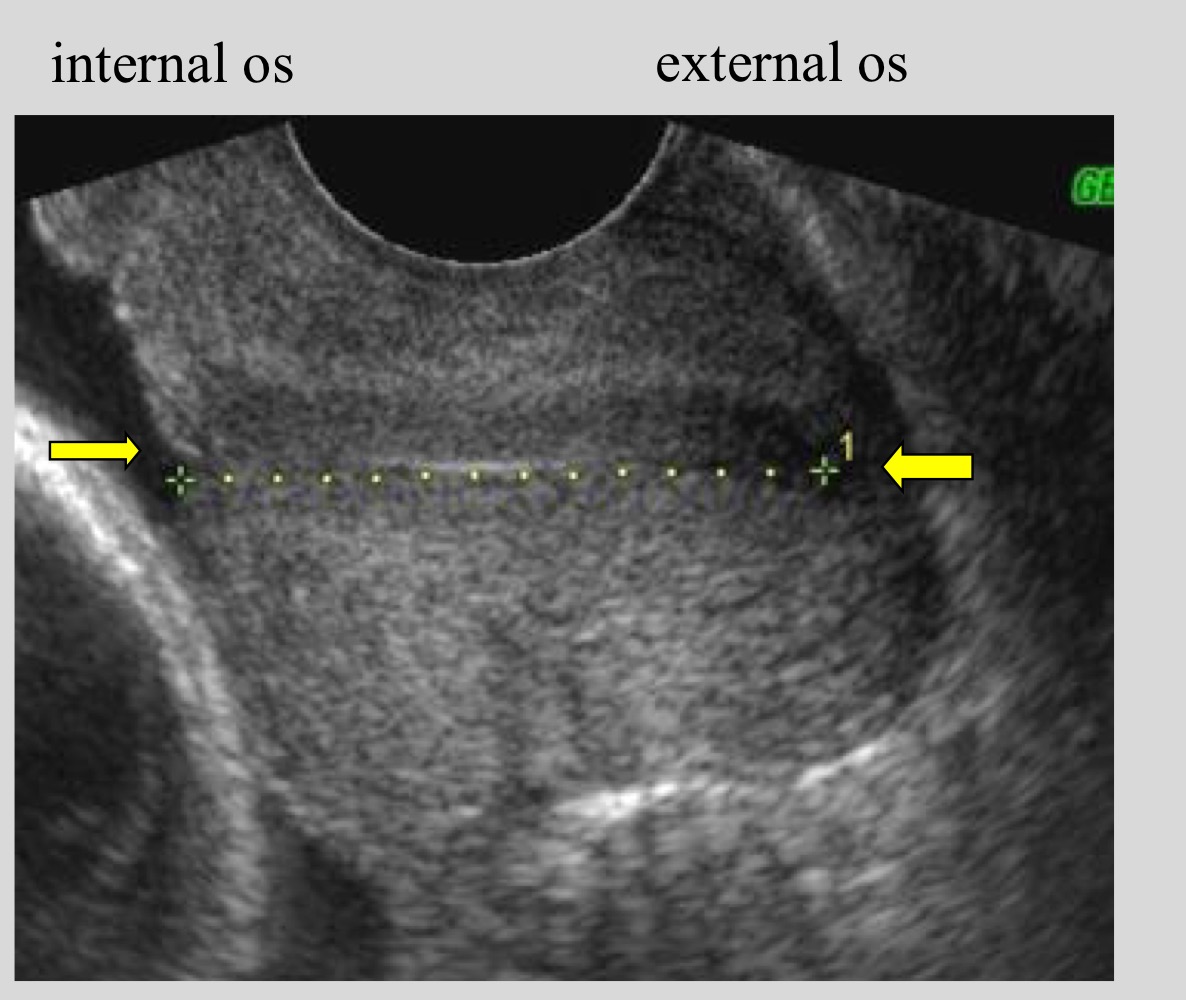

What landmarks are used to measure cervical length

Internal os to external os

What structure is used as a guide when measuring cervical length

Cervical canal

Where is the internal os located

Opposite the uterine body curve

Average normal cervical length

3.5 cm